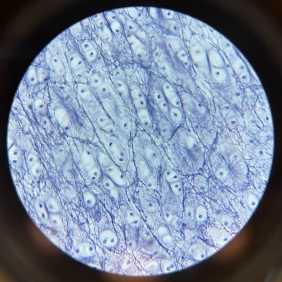

Hyaline Cartilage

Elastic Cartilage

Hyaline Cartilage